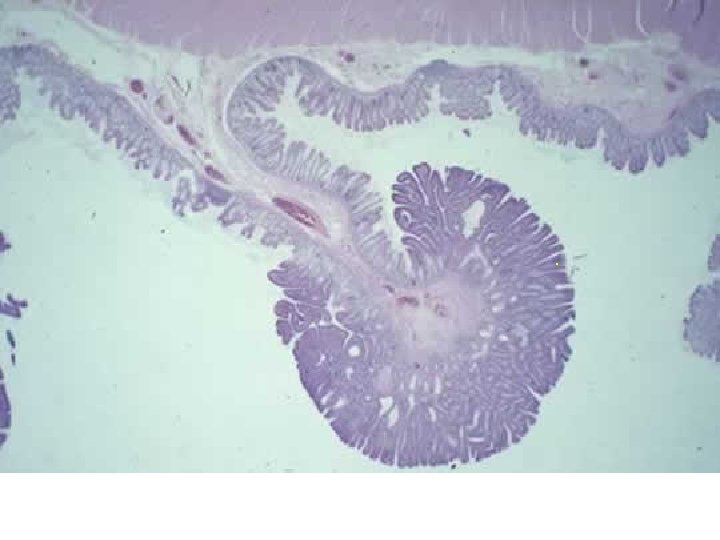

Ciliární karcinom - histologie